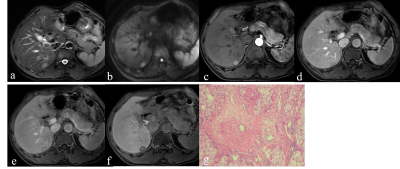

Figure 1: hepatocellular carcinoma (HCC) with central inflammatory scar.

All the 17 cases were single lesions, including inflammatory scar (n = 8), vascular scar (n = 5) and collagen scar (n = 4). Pathology revealed that the main components of three types of central scars were fibrous tissue. The mass mean maximum diameters were (53.6±20.7) mm, all masses were hyperintense on T2WI and DWI. Most masses (15/17, 88.2%) showed “wash-in with wash-out” dynamic enhancement mode, and “wash-in without wash-out” enhancement mode was rare (3/17, 17.6%). All masses were hypointense on HBP. Central scar mean maximum diameters were (20.0±10.9) mm. All central scars were mostly hyperintense on T2WI (16/17, 94.1%) and hypointense on DWI (9/17, 52.9%). Most central scars showed delayed enhancement (10/17, 58.8%), followed by no delayed enhancement (7/17, 41.2%). On HBP images, central scars mainly showed EOB "target sign" hyperintense (14/17, 82.4%), and the rest were hypointense (3/17, 17.6%). Both inflammatory and vascular scars showed hyperintense on T2WI, and collagenous scars showed hypointense (n = 1) or hyperintense (n = 3) on T2WI. Inflammatory and collagenous scars showed delayed enhancement (n = 3, n = 2,respectively) or no delayed enhancement (n = 5, n = 2,respectively), and all vascular scars showed delayed enhancement (n = 5). The maximum diameter, basic MRI signs(T2WI and DWI), and HBP findings between inflammatory, collagenous, and vascular scars were no significant differences (all P>0.05). There was a significant difference in the delayed enhancement (P=0.044).